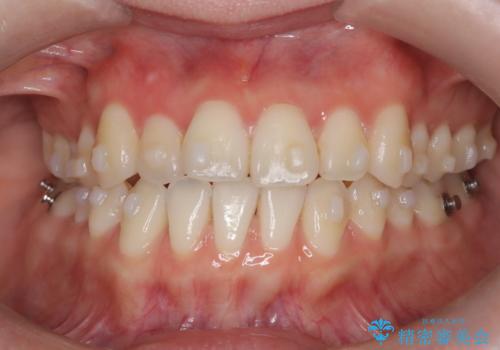

八重歯と前歯の逆の咬み合わせを、目立たない矯正で同時に改善

- 八重歯と、右上前歯(2番)が下の歯より内側に入っている反対咬合を気にされてご来院されました。精密な検査の結果、八重歯と反対咬合を同時に改善するためには、歯列全体にスペースを確保する必要があると判明。患者様のご希望から、透明で目立たないインビザライン(マウスピース矯正)による治療計画を立案しました。奥歯全体を奥へ動かす遠心移動でスペースを作り、これらの複雑な問題を一括で解消することを目指します。

今回の矯正治療では、透明なマウスピース型の装置インビザラインを使用しました。治療は、緻密なデジタル計画に基づき、奥歯から順に歯列全体を後方へ移動させる遠心移動を実施。これにより、八重歯を正しい位置に並べるためのスペースを確保しました。同時に、右上の2番を前方に誘導することで反対咬合を解消。結果として、抜歯することなく八重歯と反対咬合という複数の問題が改善され、機能的で美しい歯並びを獲得していただけました。